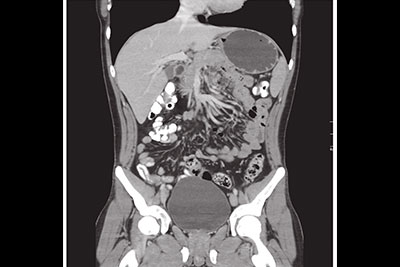

Es una técnica no invasiva e indolora que genera imágenes detalladas de cortes axiales del cuerpo a través de una exploración por rayos X. Permite diagnosticar infecciones, tumores, fracturas, infartos y hemorragias internas.

Las exploraciones por Escanografía de los órganos internos, huesos, tejidos blandos o vasos sanguíneos brindan mayor claridad y revelan mayores detalles que los exámenes convencionales de rayos X. En algunos casos puede ser necesario utilizar un medio de contraste oral o intravenoso para visualizar mejor las estructuras.

- TAC trifásico de abdomen

- Tomografía Axial Computada de Cuerpo (Tórax, abdomen, cuello o faringe, pelvis, sistema osteoarticular y de articulación temporomandibular)